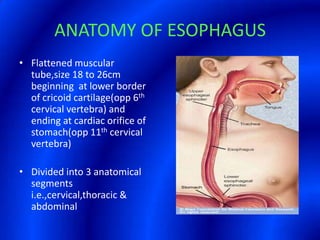

This document provides information about a barium swallow procedure. It begins with an introduction and overview of the embryology and anatomy of the pharynx and esophagus. It then describes the procedure itself, including preparation, technique, views obtained, and indications. Specific conditions that may be examined include pharyngeal and esophageal webs, foreign body impaction, scleroderma, dysphagia, mediastinal masses, and carcinoma. Diagrams are provided to illustrate normal anatomy and various pathological findings.